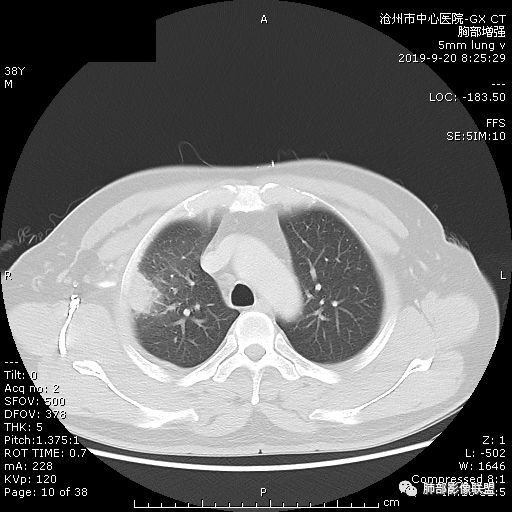

年轻男性,咳嗽2月,痰中带血,胸痛,炎症指标稍高,肿标正常。影像,右肺上叶不规则团块影,浅分叶,伴边界不清磨玻璃影,从外周向内分布,局部胸膜增厚,病灶中央坏死,坏死边界尚清,空洞形成,空洞内壁光滑;考虑炎性肉芽肿性病变,结核可能,鉴别恶性肿瘤及真菌感染。病灶分布特点不考虑隐球。

右肺上叶不规则病灶,密度不均,有分叶,边缘不清,中央有坏死,坏死壁尚光滑,增强壁有强化,病灶有外朝内,整体收缩为主,慢性病程,考虑炎性病变,肺脓肿或者结核,淋巴结肿大,支气管截断,胸膜脂肪间隙变窄,加个鉴别恶性肿瘤。

38岁,男性,慢性咳嗽2月,右胸痛8天,无发热。白细胞高,肿瘤标志物不高。右上肺不规则块状影,周围有磨玻璃影,边界模糊,整体有膨胀感,分叶,与胸膜糊墙,可疑栽赃,增强肿块中央坏死,边界清,周边强化明显,强化区有低密度影,壁不规则,跨叶生长,支气管截断,伴支气管扩张,综合考虑腺癌

晨读:右肺上叶不规则团块,深分叶,膨胀为主,有部分收缩,叶间裂牵拉上移,内多液化坏死,有支气管扩张,右肺上叶大支气管近端通畅,远端堵塞,说明肿块来源于外周,纵隔及右肺门淋巴结肿大,胸膜糊墙为主,年轻人,肿标不高,炎性指标高,综合考虑炎性肉芽肿放前面脓肿,结核,肿瘤放后面。

首先病灶示:跨尖、后、前三段,局部突入中叶;大家理解一下:是不是光滑的地方有叶裂,毛糙的地方没叶裂。

这个病变两侧受叶裂的局限,中央没有,如果是穿透叶裂的是否边缘也毛糙?事实上这叶裂边缘的叶裂是很光滑的,我倾向于这个是局部叶裂有缺陷;就是从缺陷处进来有病灶的本色:边缘毛糙;附近叶裂的阻挡,边缘光滑;既然怀疑是局部的缺陷就对良恶性没价值。

假如一个病灶直接跨越胸膜侵犯过来,应该边缘都很毛糙,不应该是最突出的地方毛糙,应该是逐步毛糙过去的,充其量越到外面毛糙越少;但事实上今天这个病变是一个很突兀的毛糙,突然间嘎然而止的毛糙;所以这个提示应该是从缺陷处跨过来的;还有今天的这个病例,病灶跨叶的部分对附近的胸膜是推移的,附近的胸膜还是很光滑,但是跨叶的病灶区很毛糙,提示跨叶部分存在胸膜缺陷可能;一般来说恶性肿瘤直接侵犯到对侧还是少的,如果这个地方你怀疑有缺陷,跨胸膜在诊断良恶性价值就不大了。